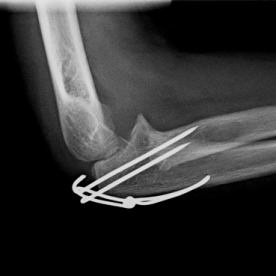

Röntgenbilder